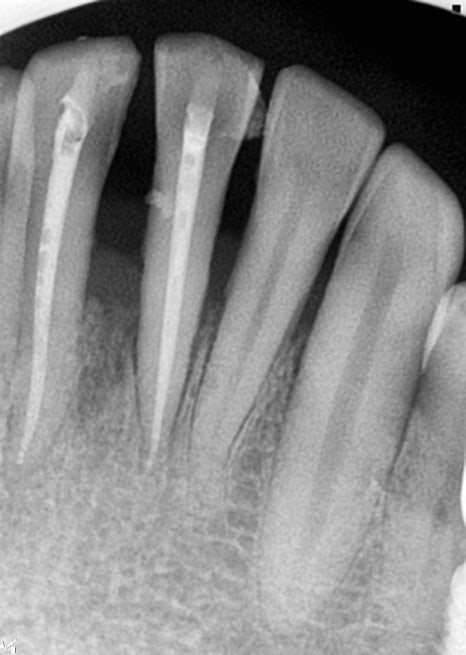

최종 앞니 보철

최종 보철은 지르코니아 크라운으로

선택하셔서 계획이 진행되었습니다.

지르코니아 크라운의 치아 색상과 투명도

잇몸의 라인 하나하나 고려를 해서

자연치아 차이가 거의 없도록

디자인 진행을 했습니다.

임시치아에도 큰 불만을 느끼지 못했다고

말씀 주셨지만 완성된 치아가

더 맘에 든다고 말씀해 주셨던 기억이 있네요.